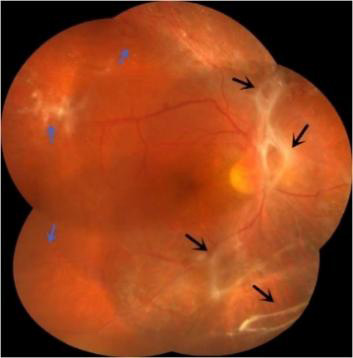

8 视网膜新生血管和视网膜增殖膜视网膜新生血管(蓝色箭头所示)和视网膜增殖膜(黑色箭头所示)

Figure 8 Neovascularization of the retina(as indicated by the blue arrow) and retinal proliferative membrane(as indicated by the black arrow)